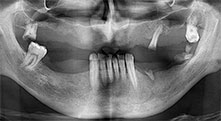

dentadura restante

Un paciente de 40 años con una dentadura restante desastrosa desea someterse a un tratamiento mediante implantes. Como es fumador, en el maxilar superior no se planea una elevación del seno con prótesis dental fija, sino una prótesis mediante puente sobre cuatro implantes anteriores.

Piezomed B6

La cresta alveolar se ranura en ambos lados mediante piezocirugía (inserto: Piezomed B6). La implantación se realiza en la misma intervención y el hueso que rodea el implante se estructura además con una regeneración ósea guiada (GBR).